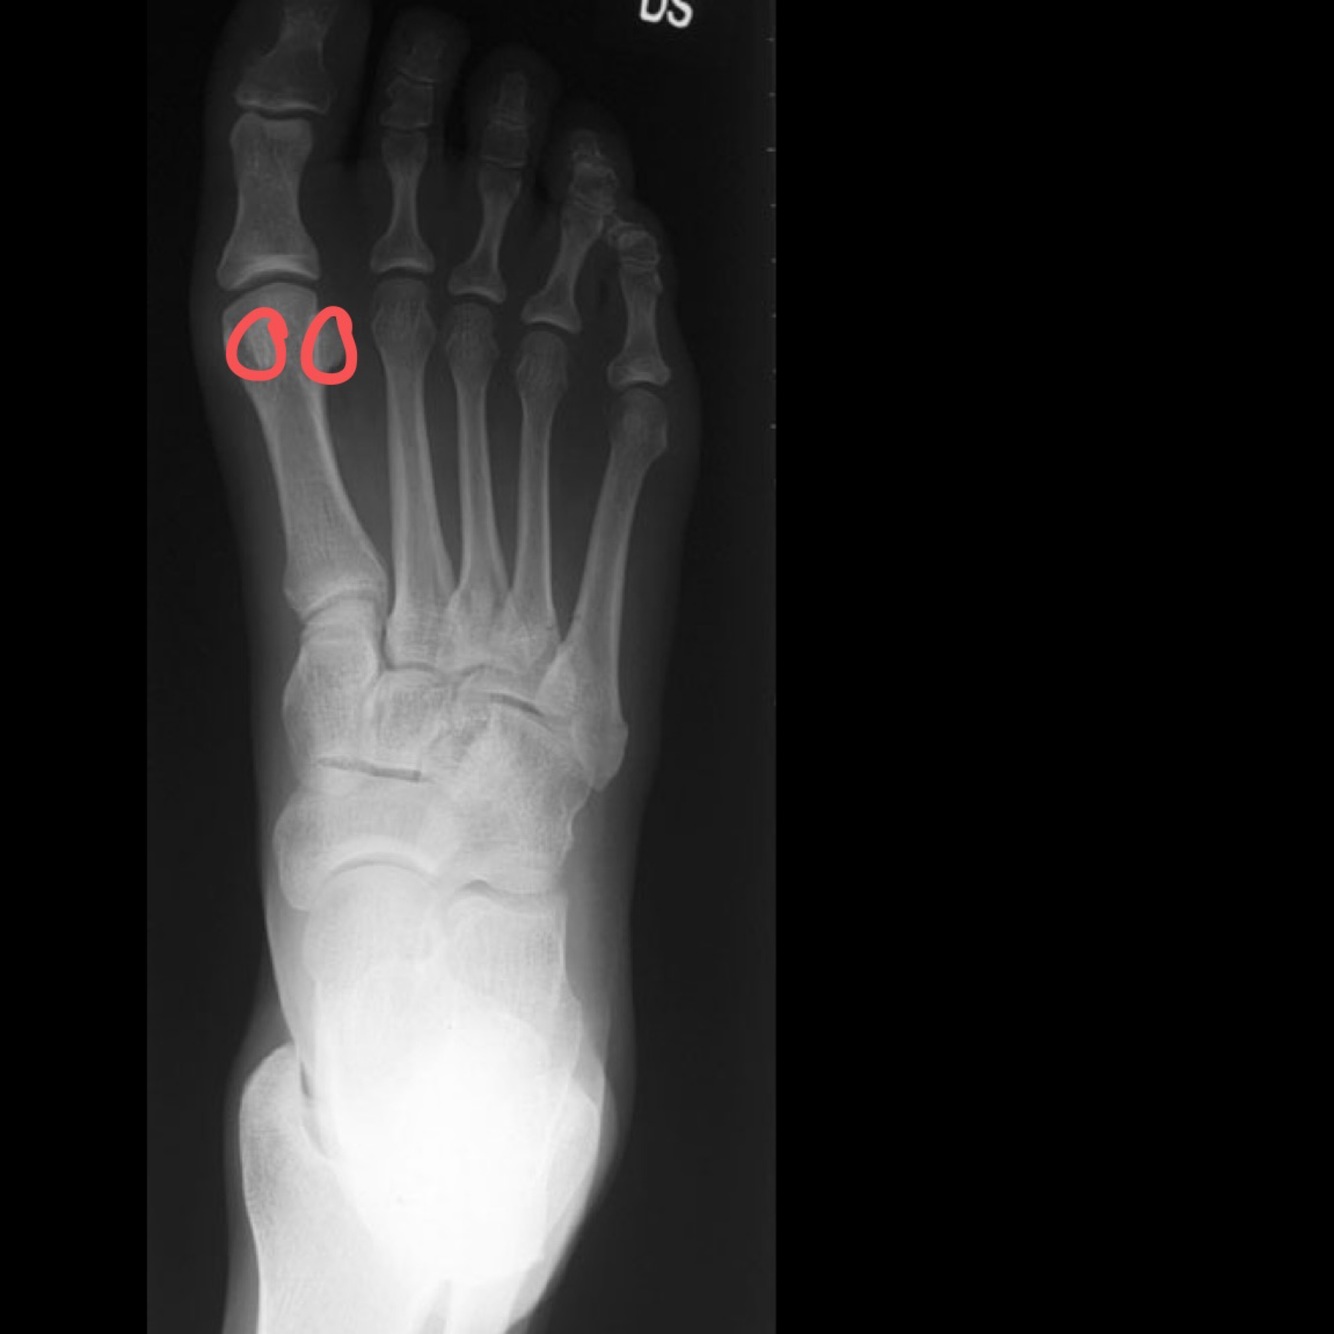

Q

Quelle vue Si je veux voir :

• Articulations de Chopart et de

Lisfranc

• Hallux valgus

• Le rebord médial du 2ième méta est

en ligne avec le rebord médial du

2ième cunéiforme

• Métatarsiens en vue planaire

• Sésamoides

A

projection dorso-planaire